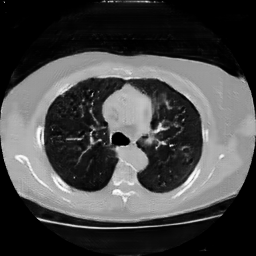

The study utilizes three 3D datasets, namely the GSP dataset[3], the LIDC-IDRI dataset[1], and the dataset employed for the Lung Nodule Analysis 2016 (LUNA16) challenge[21] which is a subset of LIDC-IDRI dataset. Samples from generated images at different stages of training are presented in Fig. 2 and Fig.3.

Refer to caption

20000

30000

40000

50000

60000

70000

80000

CRF-GAN synthetic images at different iterations

HA-GAN synthetic images at different iterations

Figure 3: Synthetic images of CRF-GAN and HA-GAN at different iterations of training on the LUNA16 dataset